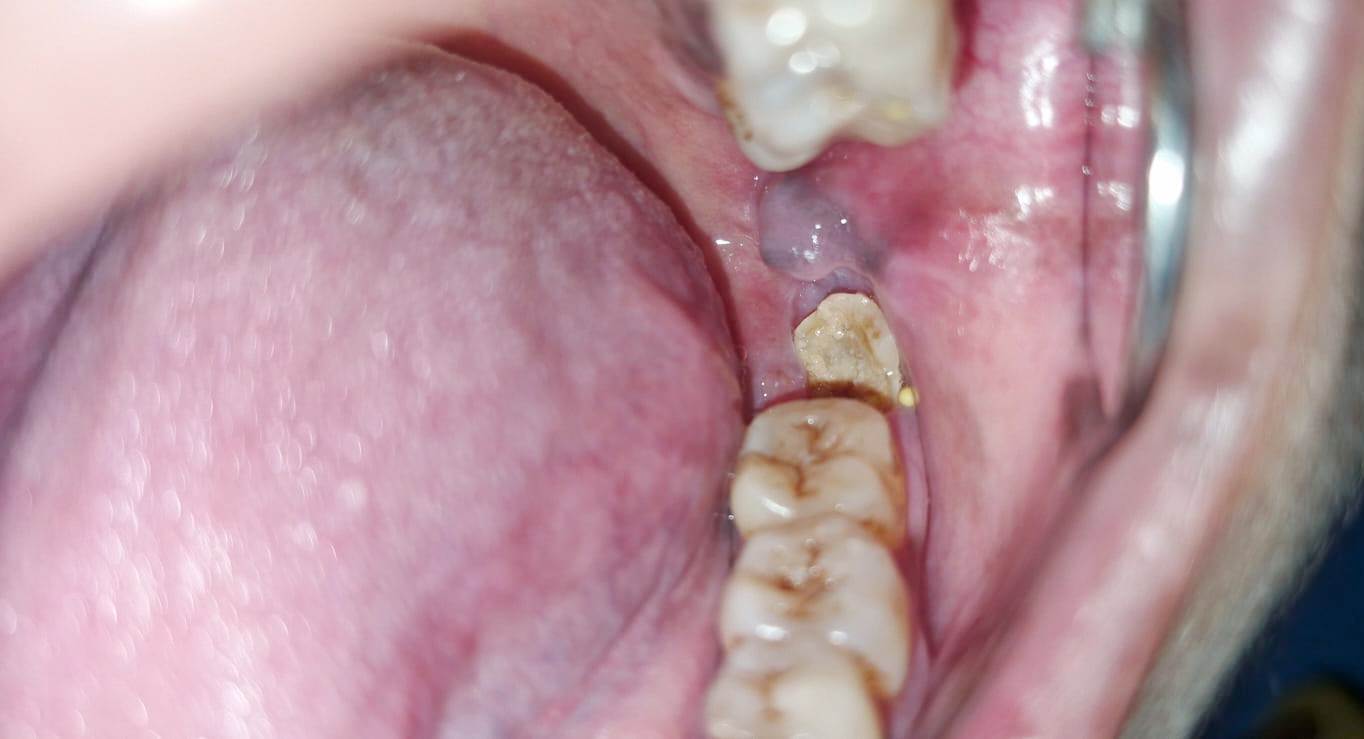

खंड चिकित्सा अधिकारी डॉ ऋषभ साव ने बताया कि अंततः सामुदायिक स्वास्थ्य केंद्र तोकापाल पहुंचने पर चिकित्सा अधिकारी (दंत) डॉ. अश्लेषा तिवारी ने गहन परीक्षण के बाद पाया कि मरीज के निचले जबड़े का अंतिम दाढ़ (मेसियोएंगुलर इम्पैक्टेड 38 मोलर) हड्डी के भीतर टेढ़ा फंसा हुआ था। इस तरह की स्थिति में दांत पूरी तरह बाहर नहीं आ पाता और वह अगले दांतों के साथ-साथ जबड़े की हड्डी पर भी दबाव बनाता है, जिसके कारण केतकी सेठी पिछले कई महीनों से न तो ठीक से भोजन कर पा रही थीं और न ही चैन की नींद सो पा रही थीं। मामले की गंभीरता को देखते हुए तत्काल सर्जिकल डिसइम्पेक्शंस और बक्कल पैड करेक्शन का निर्णय लिया। इस जटिल ऑपरेशन को डॉ. अश्लेषा तिवारी ने अपनी टीम, जिसमें सहायक सुबन नाग और सिस्टर कल्पना शामिल थीं, के साथ मिलकर अत्यंत कुशलतापूर्वक संपन्न किया। सर्जरी के माध्यम से न केवल टेढ़े फंसे दांत को निकाला गया, बल्कि आसपास के ऊतकों का सुधार भी किया गया ताकि घाव जल्दी भर सके। इस सर्जरी के सफलतापूर्वक संपन्न होने के बाद मरीज केतकी सेठी ने राहत की सांस ली है। सामुदायिक स्वास्थ्य केंद्र तोकापाल में इस स्तर की विशेषज्ञ सेवाओं की उपलब्धता ने यह साबित कर दिया है कि ग्रामीण क्षेत्रों के मरीजों को अब बड़े निजी अस्पतालों के महंगे इलाज पर निर्भर रहने की आवश्यकता नहीं है। 5 माह के लंबे दर्द के सफर के बाद केतकी को मिली इस मुस्कान के लिए उन्होंने और उनके परिजनों ने डॉ. अश्लेषा तिवारी तथा पूरी मेडिकल टीम का आभार व्यक्त किया है। अस्पताल प्रशासन ने भी टीम के इस समर्पित कार्य की सराहना करते हुए इसे संस्थान के लिए एक गौरवपूर्ण उपलब्धि बताया है।